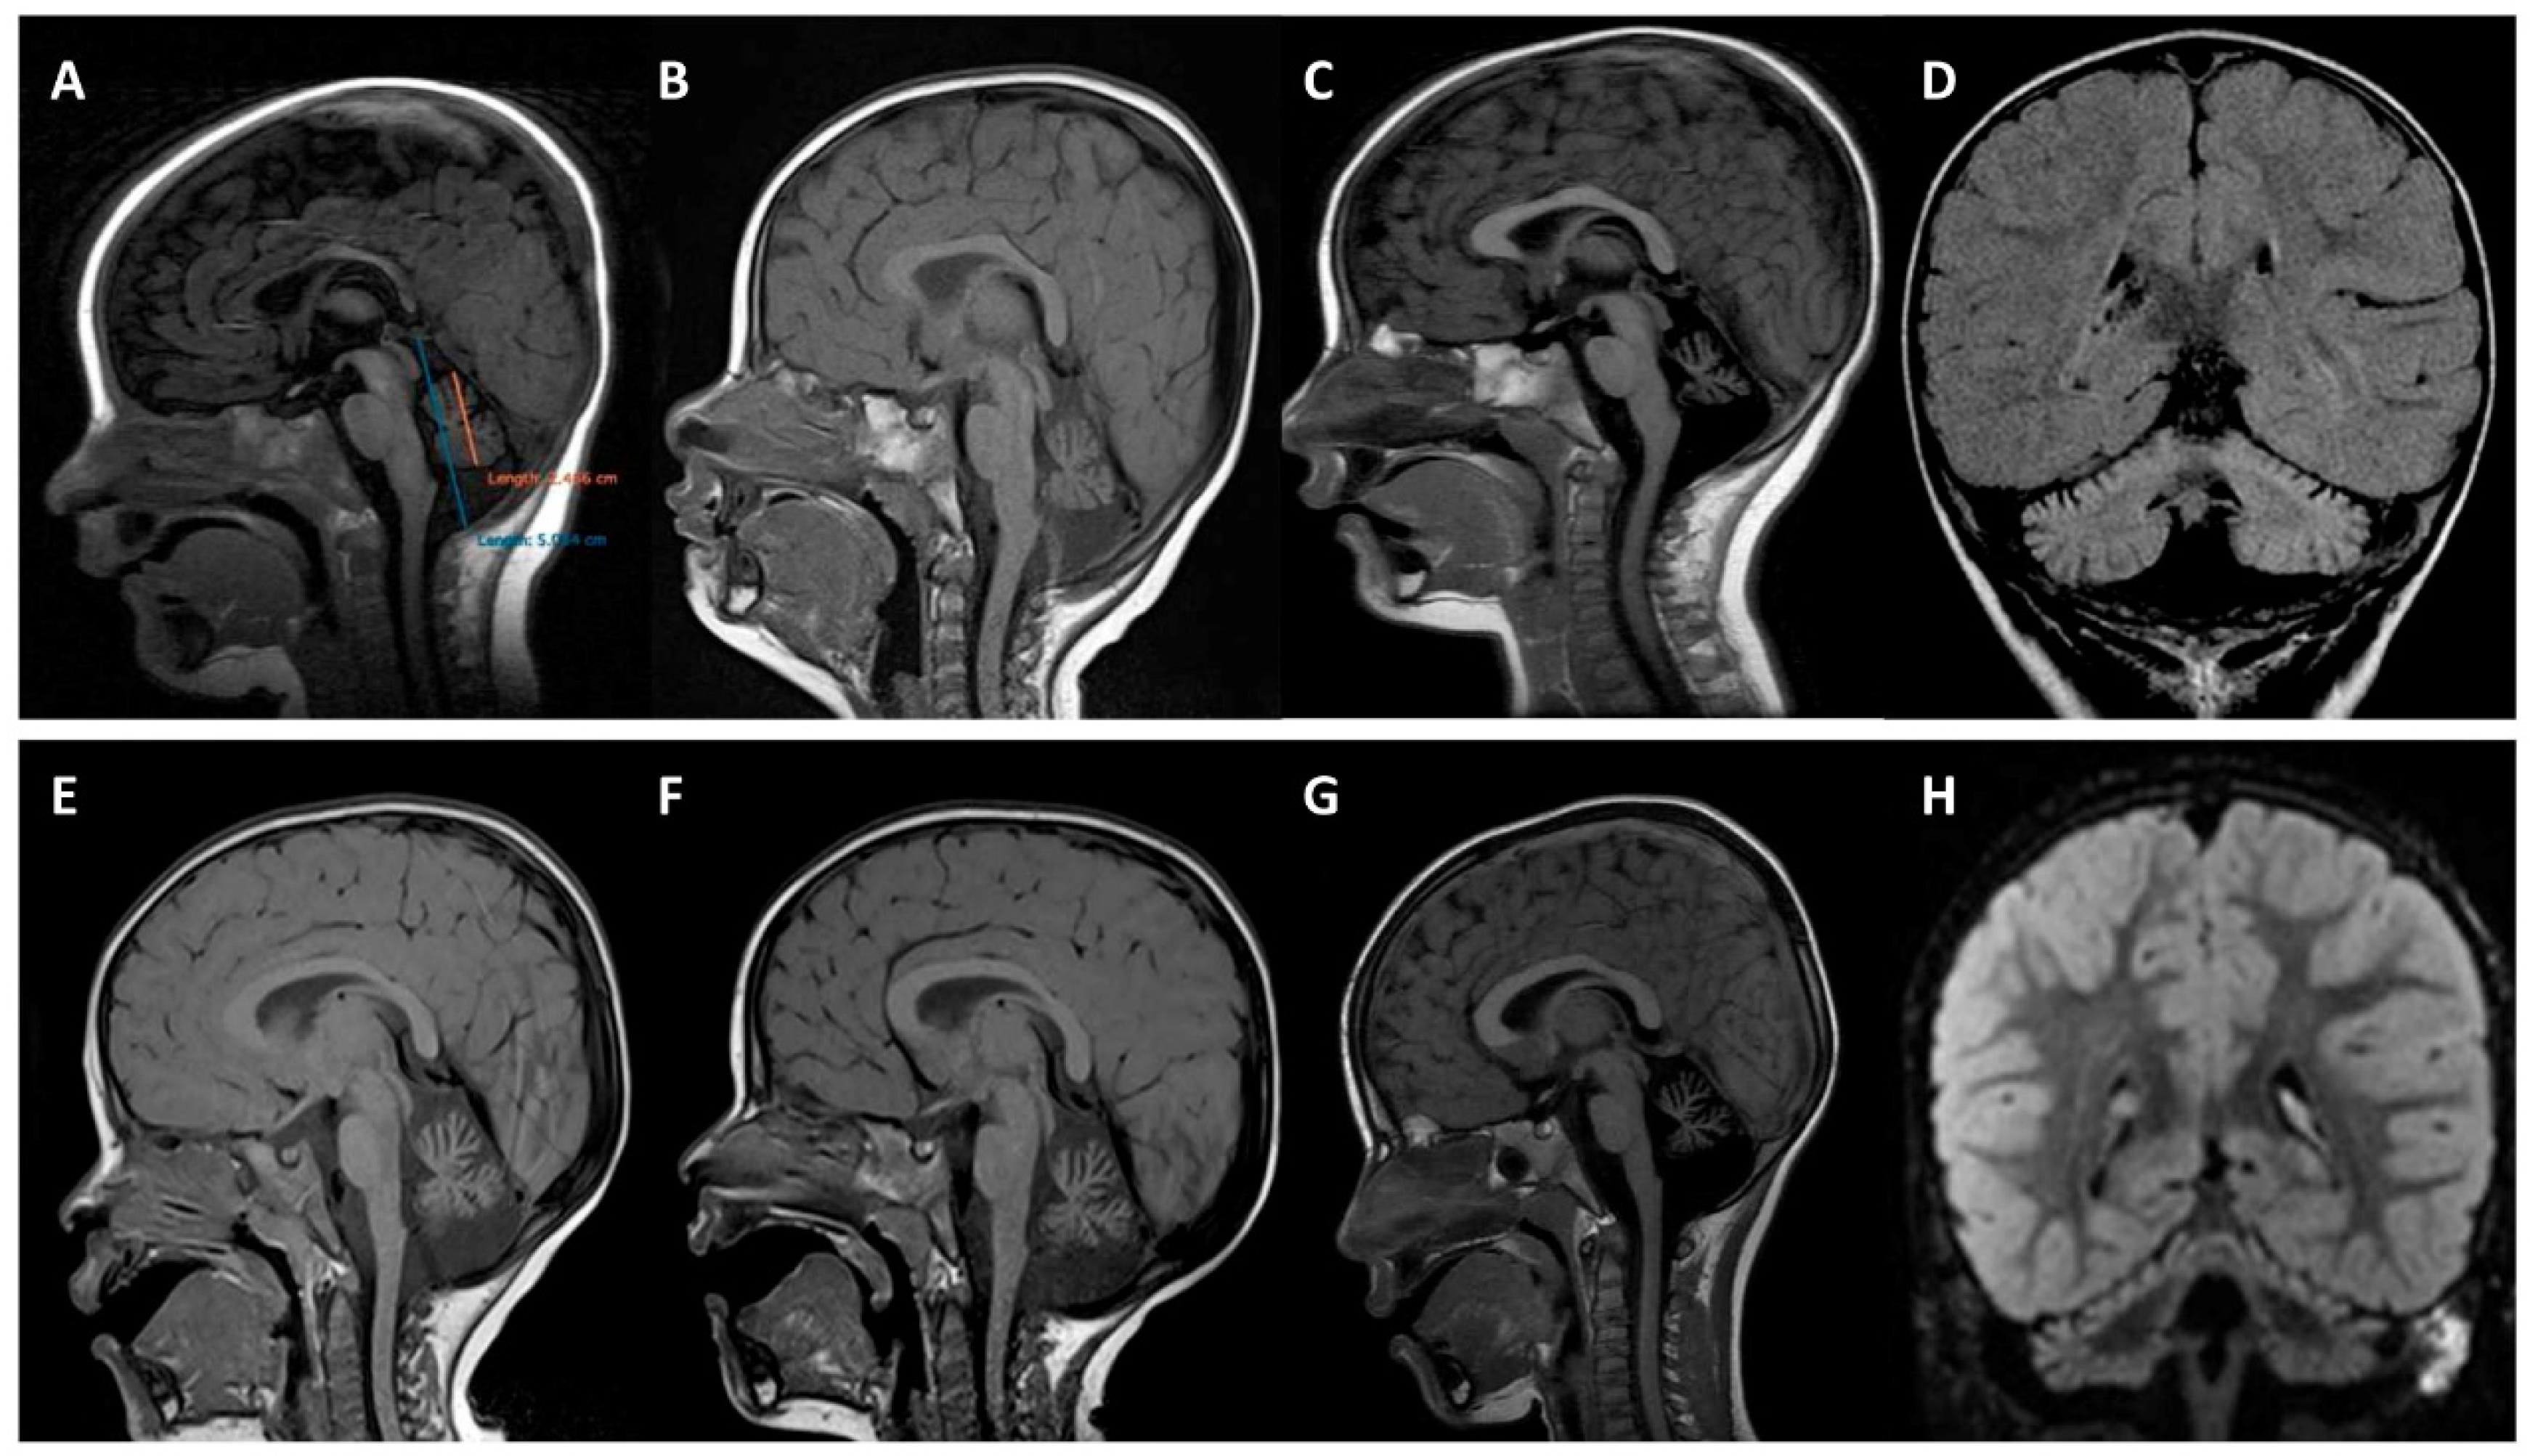

| Clinical course | Non-progressive | Non-progressive |

| Cerebellar atrophy | Progressive | Progressive |

| Cortical hyperintensity on FLAIR images | + | + |

| Additional MRI findings | - | - |